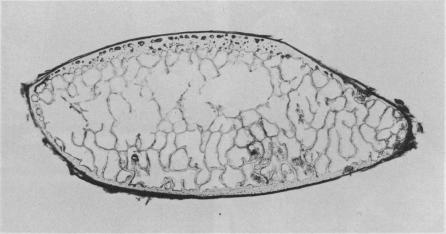

Nineteen lactating or recently weaned sows that had a history of lameness, weakness or paralysis were studied at necropsy. Ten sows had osteoporosis and pathological fractures while six had lumbar vertebral osteomyelitis. Values for bone ash, specific gravity of bone and the cortical to total ratio were significantly reduced in sows with osteoporosis and pathological fractures.

对19头有跛行、虚弱或瘫痪病史的泌乳期或刚断奶母猪进行了尸检研究。10头母猪患有骨质疏松症和病理性骨折,6头患有腰椎骨髓炎。患有骨质疏松症和病理性骨折的母猪的骨灰、骨比重以及皮质骨与总骨量的比率值显著降低。